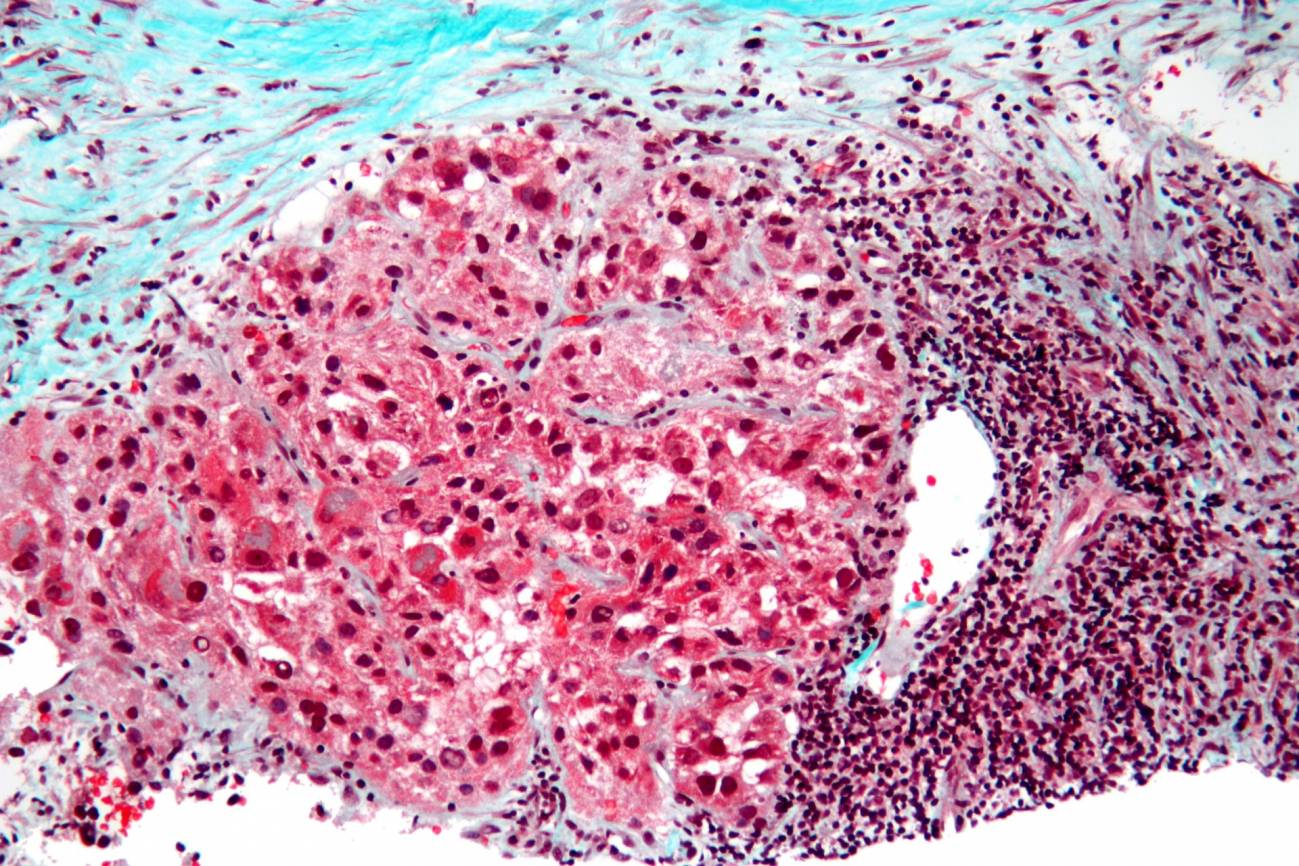

Encuentran microproteínas presentes exclusivamente en el cáncer de hígado, lo que podría servir para el diseño de vacunas

Una investigación liderada desde el Instituto de Investigación del Hospital del Mar (Barcelona) y con participación de investigadores del CIMA (Universidad de Navarra) y de la Universidad Pompeu Fabra (Barcelona) ha desvelado la existencia de microproteínas presentes de forma prácticamente exclusiva en el carcinoma hepatocelular, la forma más común de cáncer de hígado. Estas estructuras, que parecen encontrarse en un porcentaje significativo de pacientes, podrían servir para el desarrollo de vacunas específicas frente a este tipo de tumores. Los resultados se publican en la revista Science Advances.